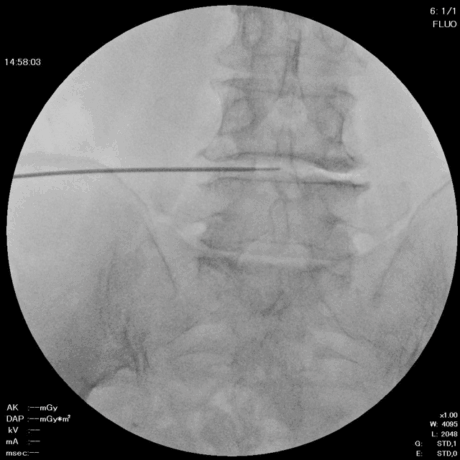

5. 線維輪の熱凝固(コアグレーション)

椎間板の線維輪に生じた亀裂部に対して、3〜6方向に5秒ずつ熱凝固を行います。

DISC-FX:6方向 × 各6秒

DART:3方向 × 各6秒